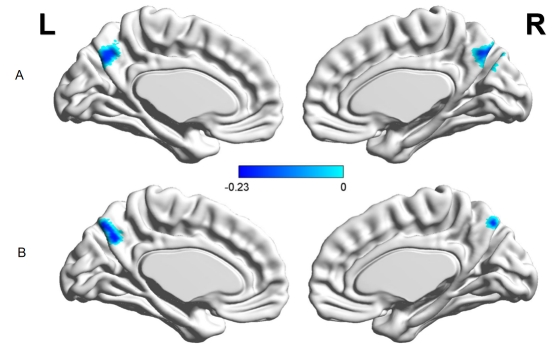

近日,西南大学365上市公司(英国)集团冯廷勇教授团队在国际著名行为科学期刊Cortex(中科院SCI二区,行为科学Top期刊)上发表了题为“The functional connectivity between right parahippocampal gyrus and precuneus underlying the association between reward sensitivity and procrastination”的学术论文。本研究采用基于体素的形态学分析(VBM)和静息态功能连接(rsFC)相结合的多模态分析方法来探索奖励敏感性与拖延之间联系的神经基础。为了验证结果的稳定性,本研究采用两独立样本进行交叉验证。在两个独立样本中均发现,(1)在行为结果方面,奖励敏感性与拖延成正相关关系(见图1)。(2VBM分析发现,右侧旁海马的灰质体积与奖励敏感性得分成正相关关系(见图2),并且在两个独立样本中发现右侧旁海马区域存在重叠区域,这说明右侧旁海马可能是奖励敏感性的神经基础(见图3)。(3rsFC分析发现,右侧旁海马-楔前叶的功能连接与奖励敏感性成负相关关系(见图4),并且在两个独立样本中得到验证(见图5)。(4)中介分析结果发现,右侧旁海马-楔前叶的功能连接在奖励敏感性与拖延的关系中起到中介的作用(见图6)。

4 rsFC结果:右侧旁海马与楔前叶的功能连接与奖励敏感性成负相关(图A,样本1;图B:样本2)。